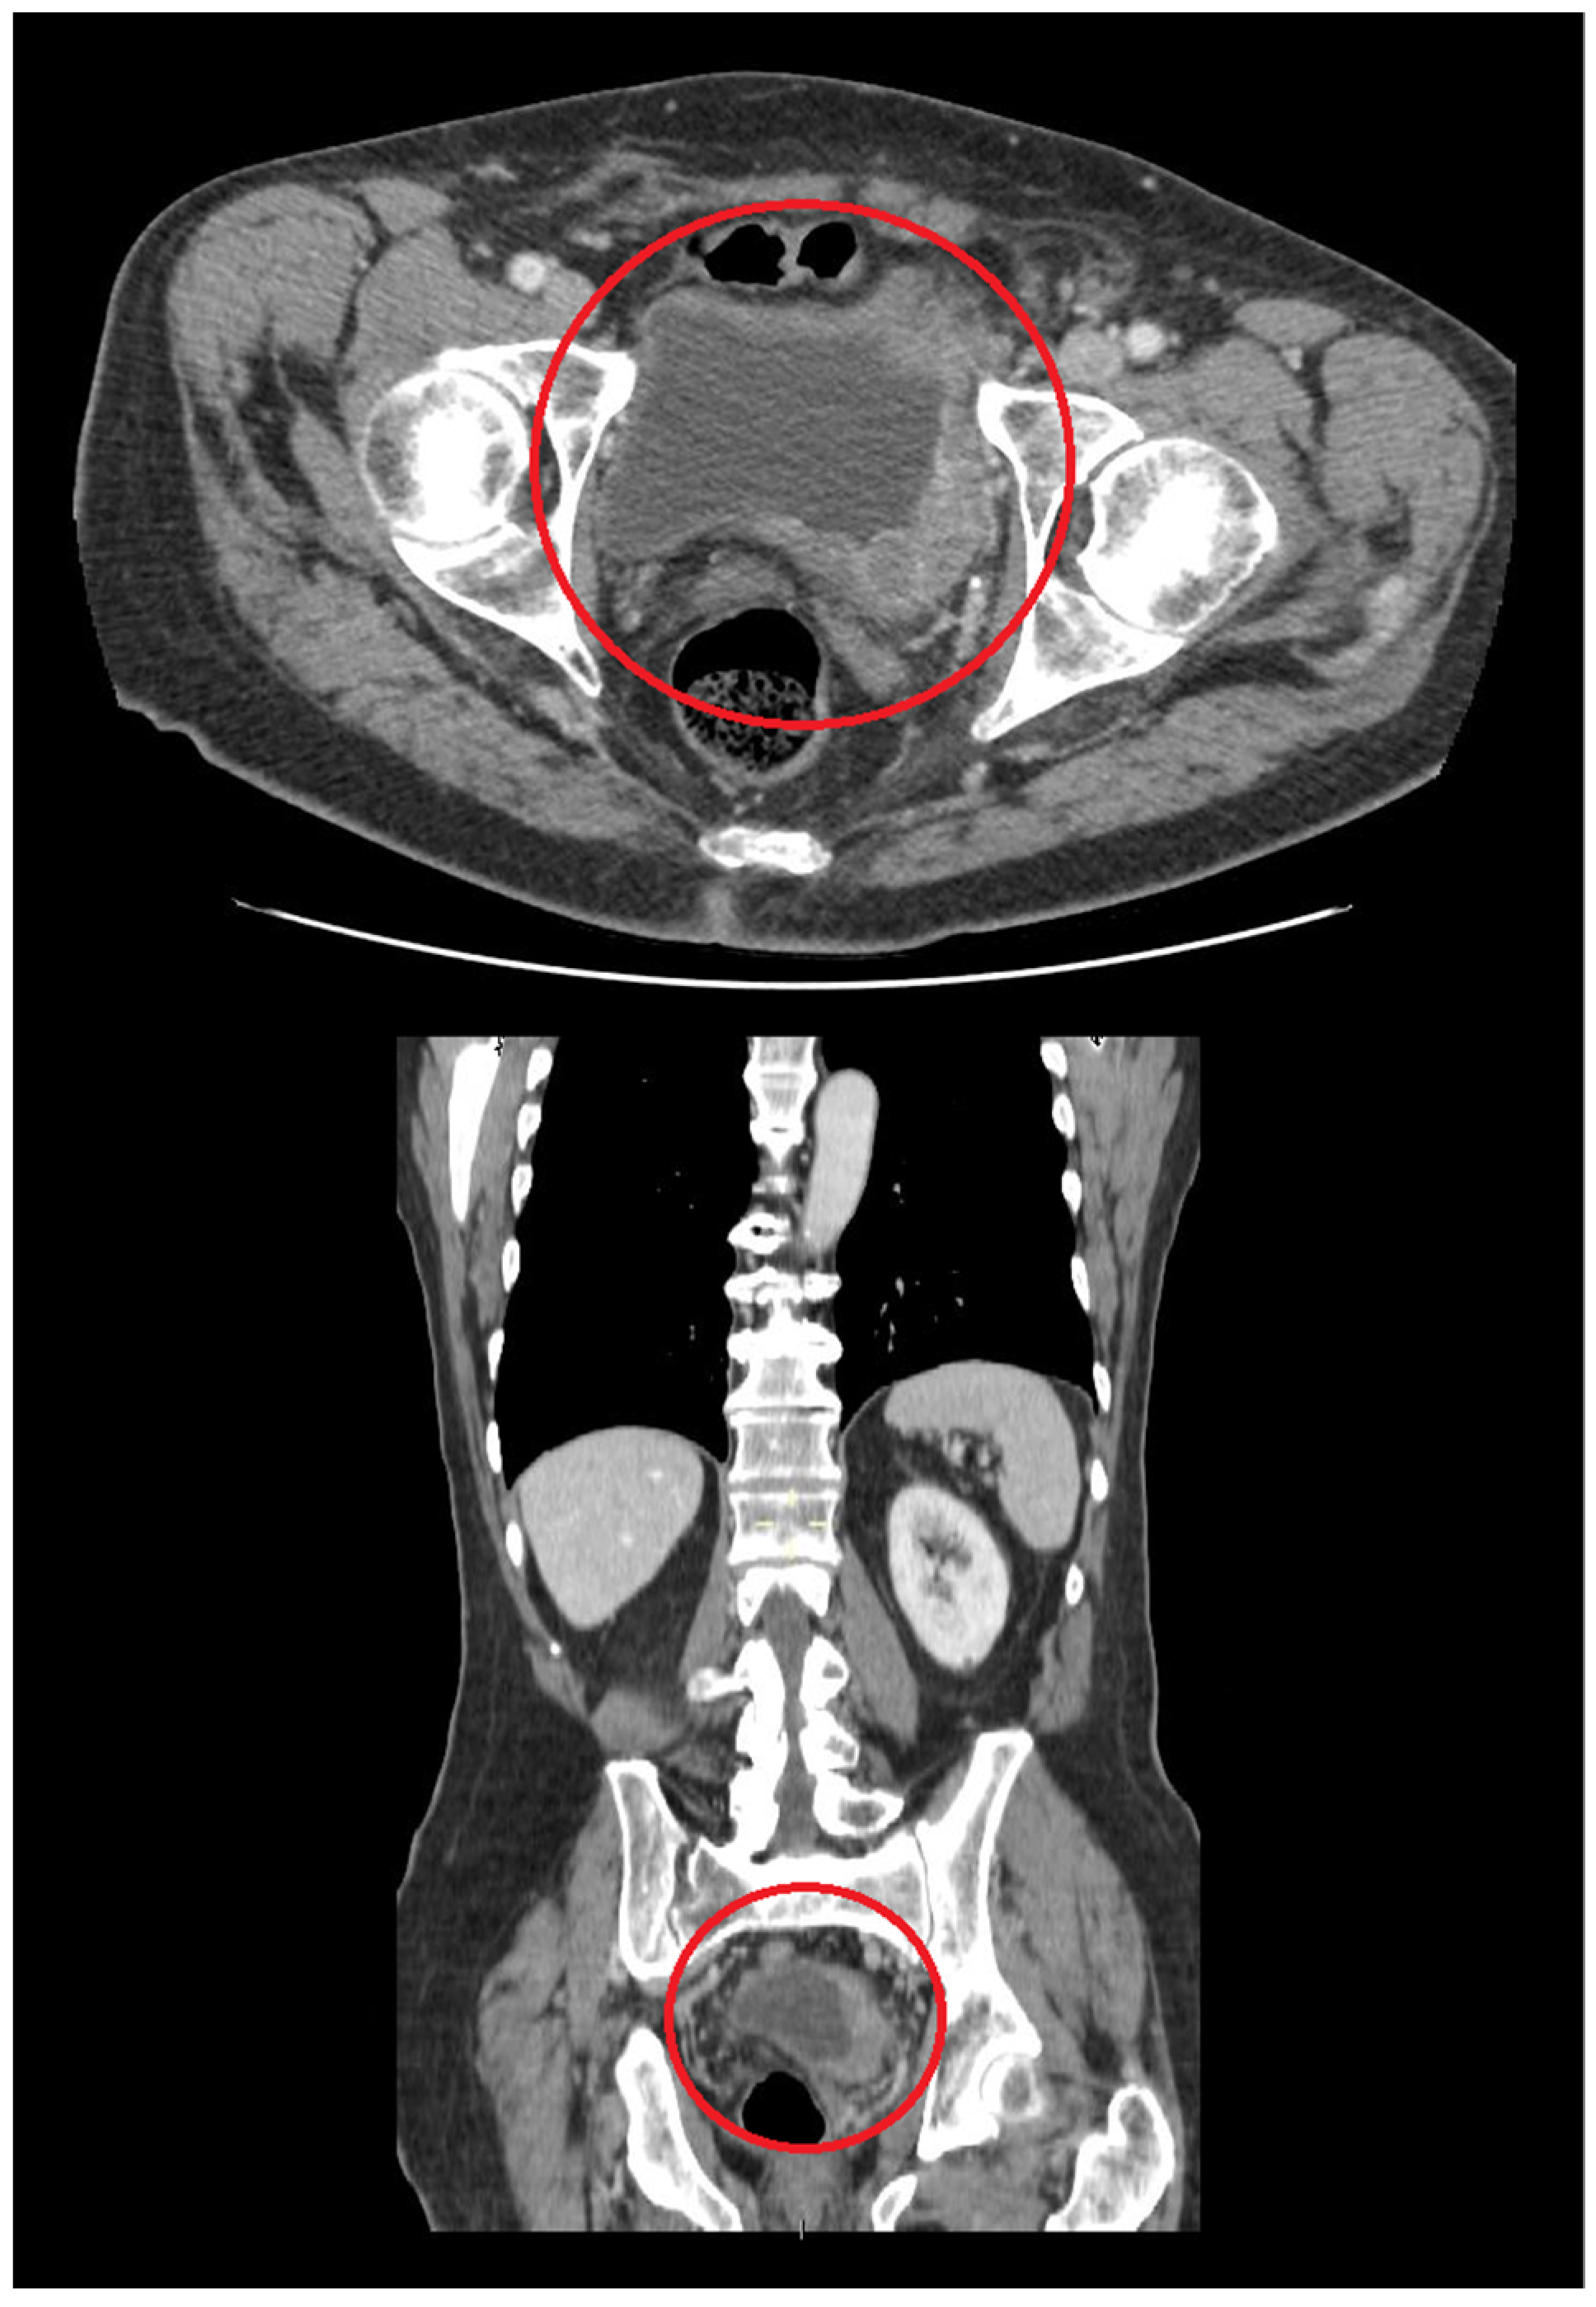

3. Primary DLBCL of the Urinary Bladder: Clinical Features

4. Diagnostic Approach for Primary Urinary Bladder Lymphoma